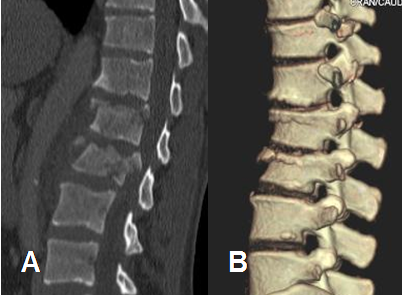

La principal indicación para realizar tomografía axial computarizada (TAC), es el trauma. Las reconstrucciones 3D son de mucha utilidad para detectar y caracterizar las fracturas. (Fig 14).

Fig 14. Fractura con reconstrucción 3D.

A: TAC reconstrucción sagital y B: TAC reconstrucción 3D. Fracturas por compresión en la parte anterior de los cuerpos de D12, L1 y L2.